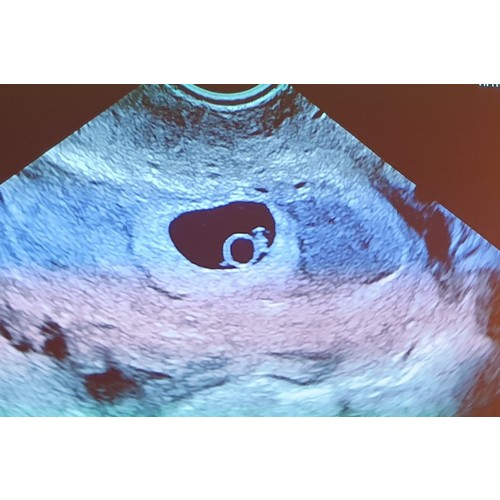

Dit konden wij zien op 5weken 4dagen.

Op de echo zelf zagen wij wel de vruchtzakjes al.

Vandaag een echo gehad en ze schat in dat ik tussen de 5,5-6 weken zwanger ben. Uitwendig zag ze wel wat, maar inwendig was het beter te zien en hebben we het hartje zien kloppen.